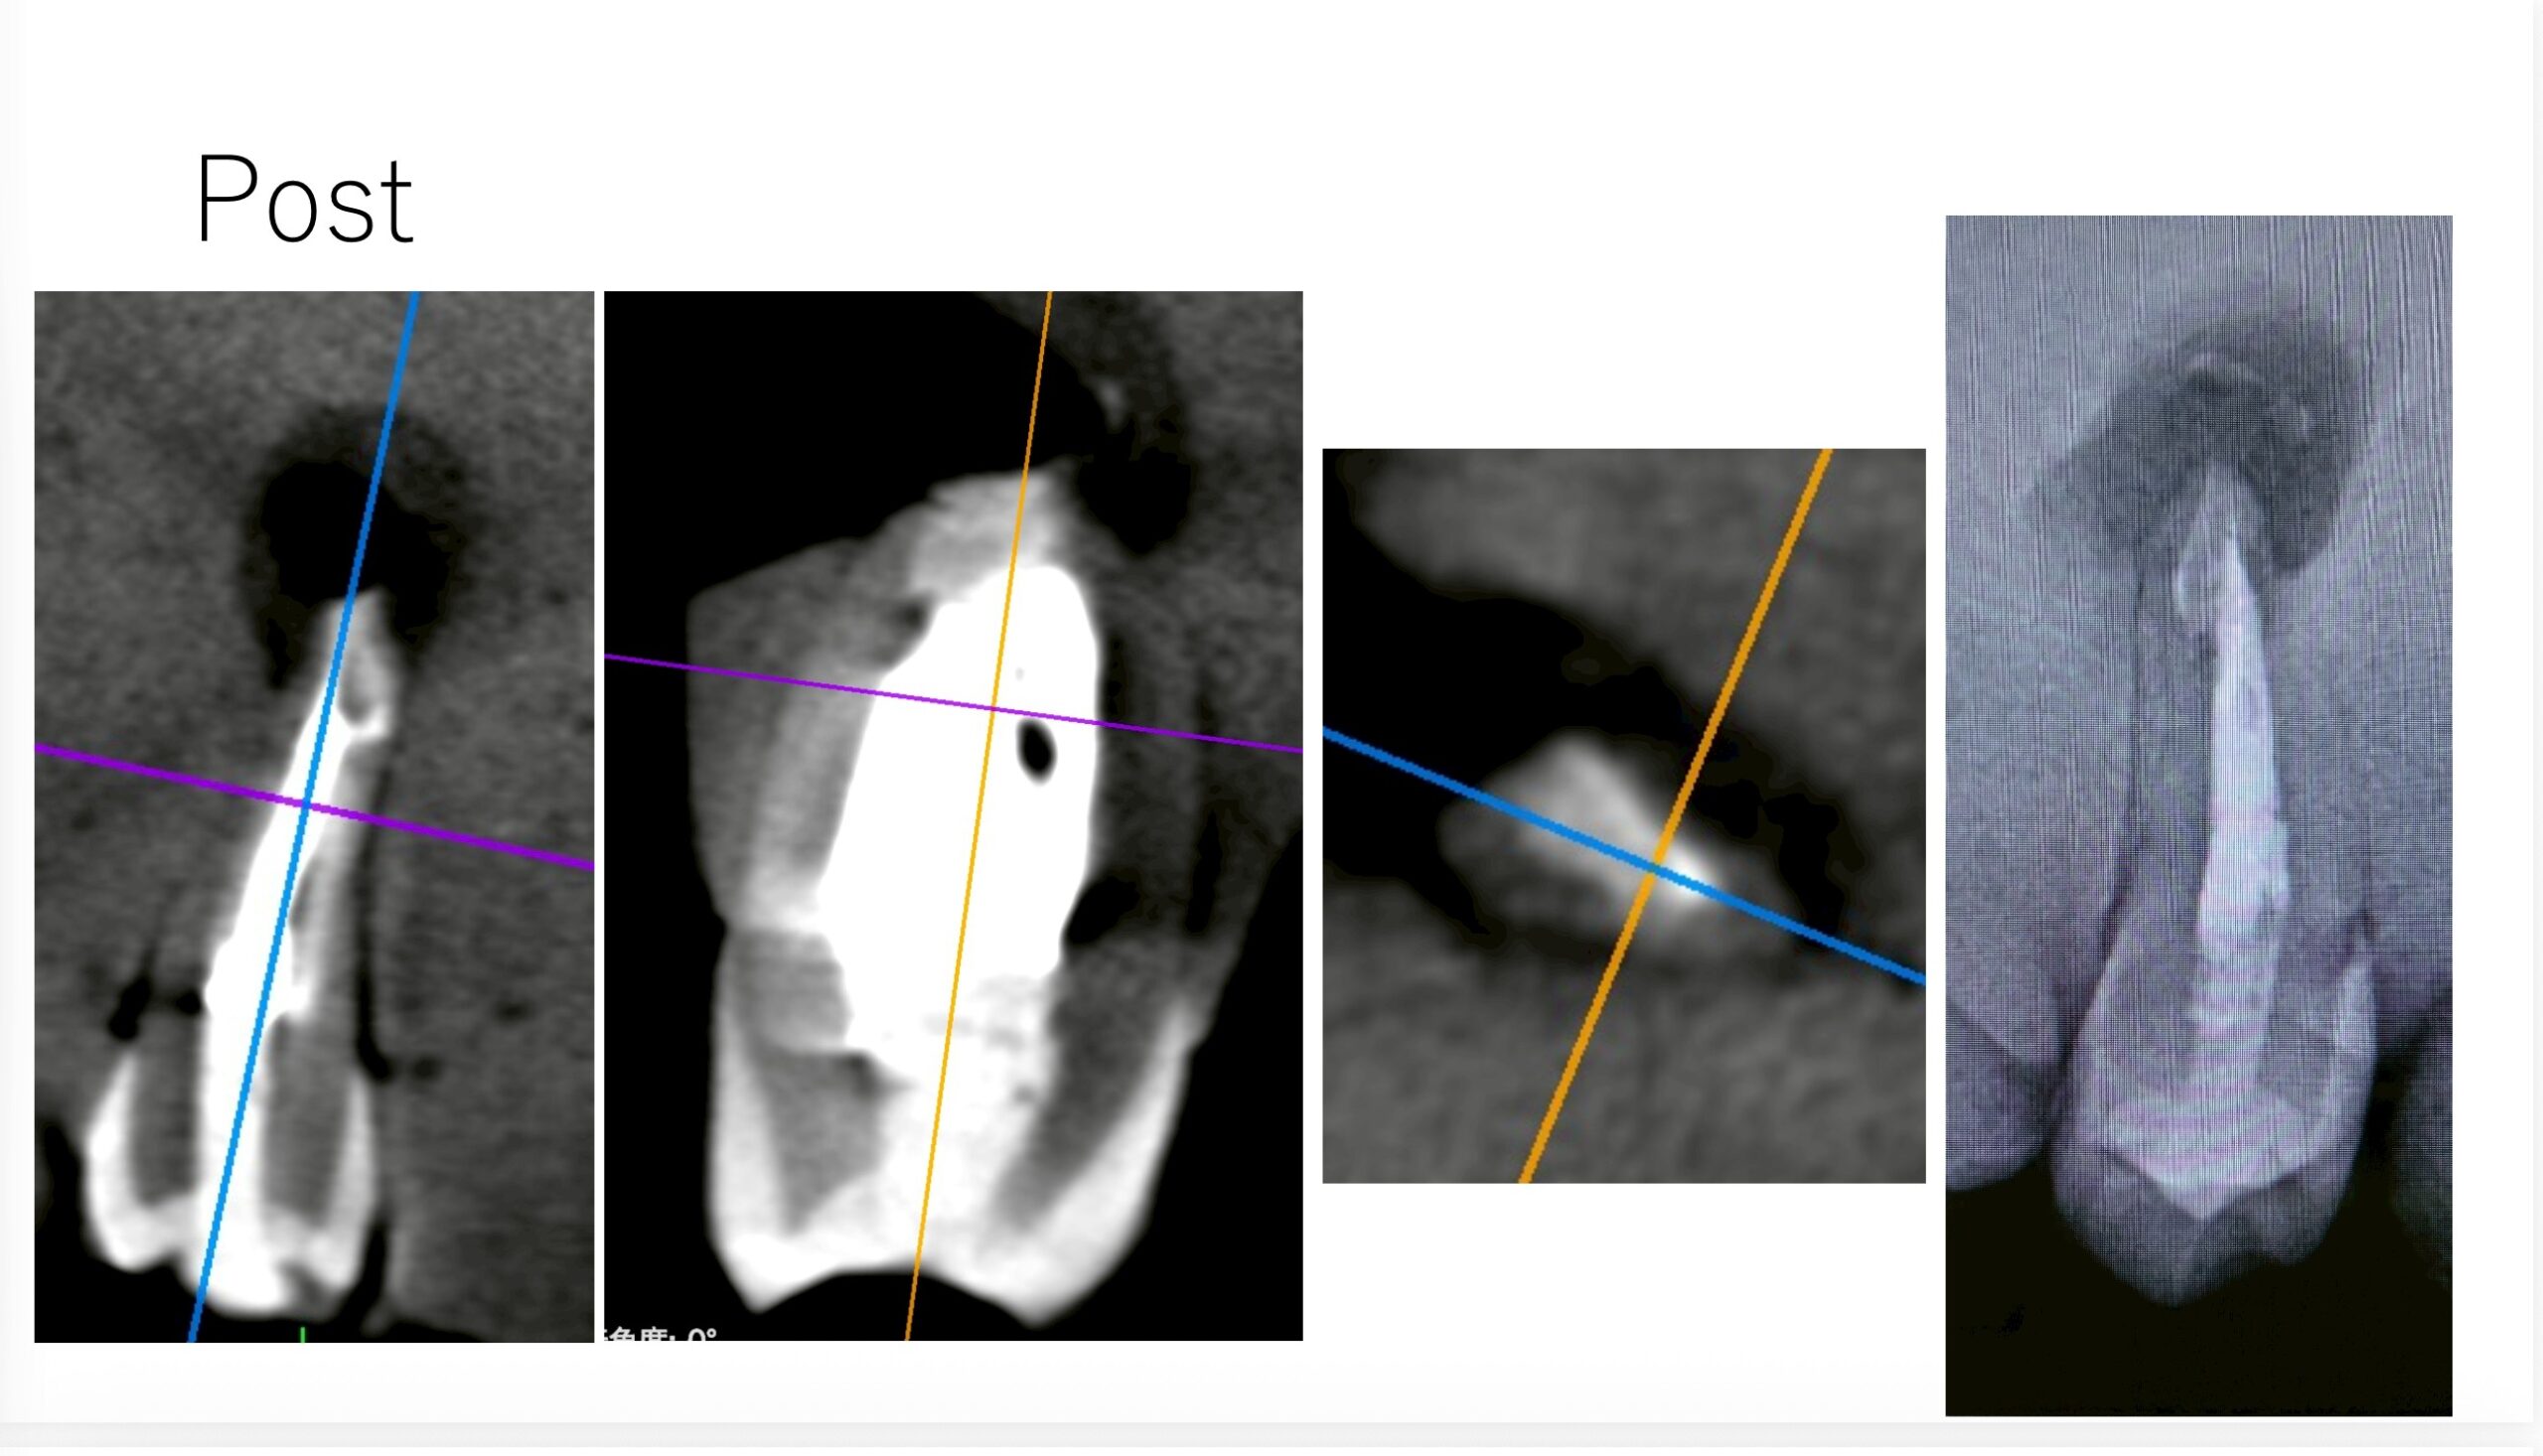

次の受講者は以下だ。

これでも治癒することはこのHPのBlogで示しているが、

他県(遠方)からの患者さん。。。前歯の歯茎が痛く、ここで治療すると1回で終了すると言われたので来た〜#7 Apicoectomyとその1yr recall

USCだとしょっぱいからやり直せと言われる案件だ。

この受講者は外科に関してはもう教えることはないだろう。